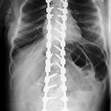

Хирурзите извършват оперативната интервенция на гръбнака, като поставят стандартна растяща система, която трябва да бъде разтягана оперативно на всеки шест месеца, за да може Лора да продължи да расте, докато достигне необходимата костна зрялост за осъществяването на окончателна стабилизация. Седмица по-късно детето е подложено и на операция на тазобедрените стави. След повторна хирургична намеса за ревизиране на тази в областта на ставите, както и три дистракции (оперативно разтягане на имплантите) на гръбнака, детето е в инвалидна количка, изпитва силни болки в гърба и има подутина в същата област.

След извършване на клиничен преглед и необходимите образни изследвания става ясно, че имплантираната система е компрометирана и една от пръчките е счупена. В този случай, освен силната болка, която детето изпитва, съществуват рискове от настъпване на редица усложнения като – неврологични усложнения (пареза, парализа), псевдоартроза (несрастване на костта), прогресия на гръбначната деформация, инфекции и др. Това налага системата да бъде ревизирана и изцяло сменена в много кратки срокове.

Проф. Яблански и неговият екип извършват ревизията и сменят компрометираната стабилизация, като поставят окончателна такава, чрез задна вертебродеза (Spinal Fusion) -„златен“ стандарт при хирургично лечение на деца със сколиоза в световен мащаб. При сливане (Fusion) на гръбначния стълб, изкривените прешлени зарастват заедно, за да създадат единична солидна кост в парвилна позиция.